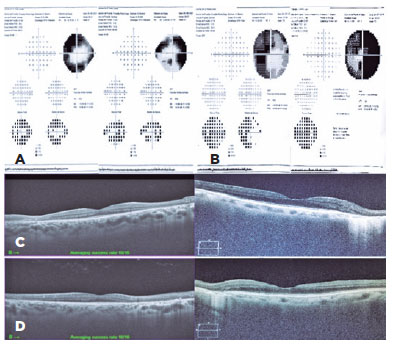

A computerized visual field test revealed the presence of deep arcuate scotoma in the right eye and ring-shaped scotoma in the left eye, which corresponded to the areas of atrophy and pigment accumulation (Figure 2A).

Autofluorescence revealed hypoautofluorescence along the retinal veins and hyperautofluorescence lines outlining the hypoautofluorescent areas (Figure 1B).

OCT of the maculas revealed preserved foveal profile, average macular thickness, and intact retinal layers. In the areas of the lesions, there was a loss of the outer retinal layers (Figure 2C).

Her best-corrected visual acuity was 20/40 in both eyes and her potential acuity meter was 20/20 in both eyes. Slit-lamp examination revealed a symmetric cataract (nuclear 2+/4+) and no other abnormalities in the anterior segment. Fundoscopy disclosed retinal pigmented epithelium (RPE) atrophy and pigmentary clumps around the optic disc and following the pathway of blood vessels, sparing the maculas (Figure 1C). FAF showed geographic hypoautofluorescence along with the paravenous areas and no areas of hyperautofluorescence (Figure 1D). OCT showed the loss of the outer retinal layers in the areas of the lesions (Figure 2D) and a computerized visual field test revealed a ring-shaped scotoma in both eyes (Figure 2B). Systemic screening for infectious or rheumatic diseases was negative, with no family history of ocular diseases.